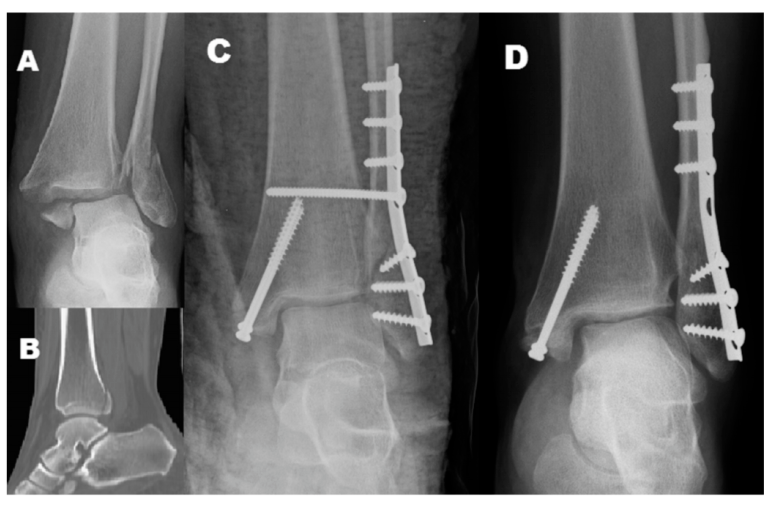

图2:三踝骨折患者,后踝未固定,术后6周取去下胫腓螺钉

我们回顾了2013年1月至2017年12月间接受双踝(不含PMF)或三踝(含PMF)骨折切开复位内固定治疗并伴有下胫腓联合损伤的患者,并进行至少24个月的术后随访。所有患者均出现下胫腓联合不稳定,并使用下胫腓联合螺钉进行治疗,PMF未固定。第一组为术后6-8周移除下胫腓联合螺钉的双踝骨折患者,第二组为术后6-8周移除下胫腓联合螺钉的三踝骨折患者,第三组为术后3个月移除下胫腓联合螺钉的三踝骨折患者。分析人口统计学数据、临床和影像学结果。

共纳入113例患者(第一组47例,第二组43例,第三组23例)。三踝骨折患者(第二组和第三组)的PMF平均大小为14%。各组间踝关节功能结果无显著差异。下胫腓不稳定的复发率在第一组为10.6%,第二组为20.9%,第三组为8.7%。虽然三组间下胫腓联合不稳定的复发率差异无统计学意义(P=0.264),但与其他两组相比,第二组在术后首次X光片和最后一次随访X光片之间的胫腓骨间隙显示出更多的间隔变化(P=0.028)。骨折均愈合,无下胫腓螺钉断裂患者。

[Results: A total of 113 patients were included (Group I, n=47; Group II, n=43; Group III, n=23). Average size of PMF was 14% in patients with tri-malleolar fractures (Groups II and III). No significant difference in ankle functional outcome among groups was observed. The recurrence rate of syndesmotic instability was 10.6% in Group I, 20.9% in Group II, and 8.7% in Group III. Although the difference in recurrence rates of syndesmotic instability among three groups was not statistically significant (P=0.264), Group II showed more interval change in tibiofibular clear space between initial postoperative radiographs and last follow-up radiographs (P=0.028) compared to the other two groups. Fracture union was achieved in

all patients without screw breakage.]